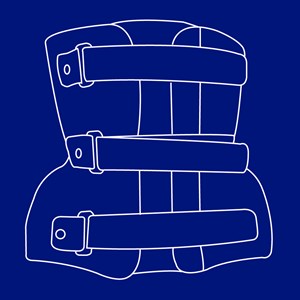

BOB-korset

Type: pdf

Størrelse: 1158 KB